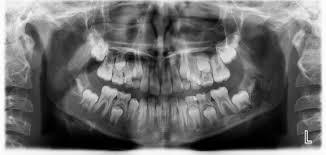

Dentaltown Boy 9 Years Old Referred For Panorex X Ray Due To Unerupted First Molar A Complex Odontoma Also Cal Dental Hygiene School Dental Humor Dentistry